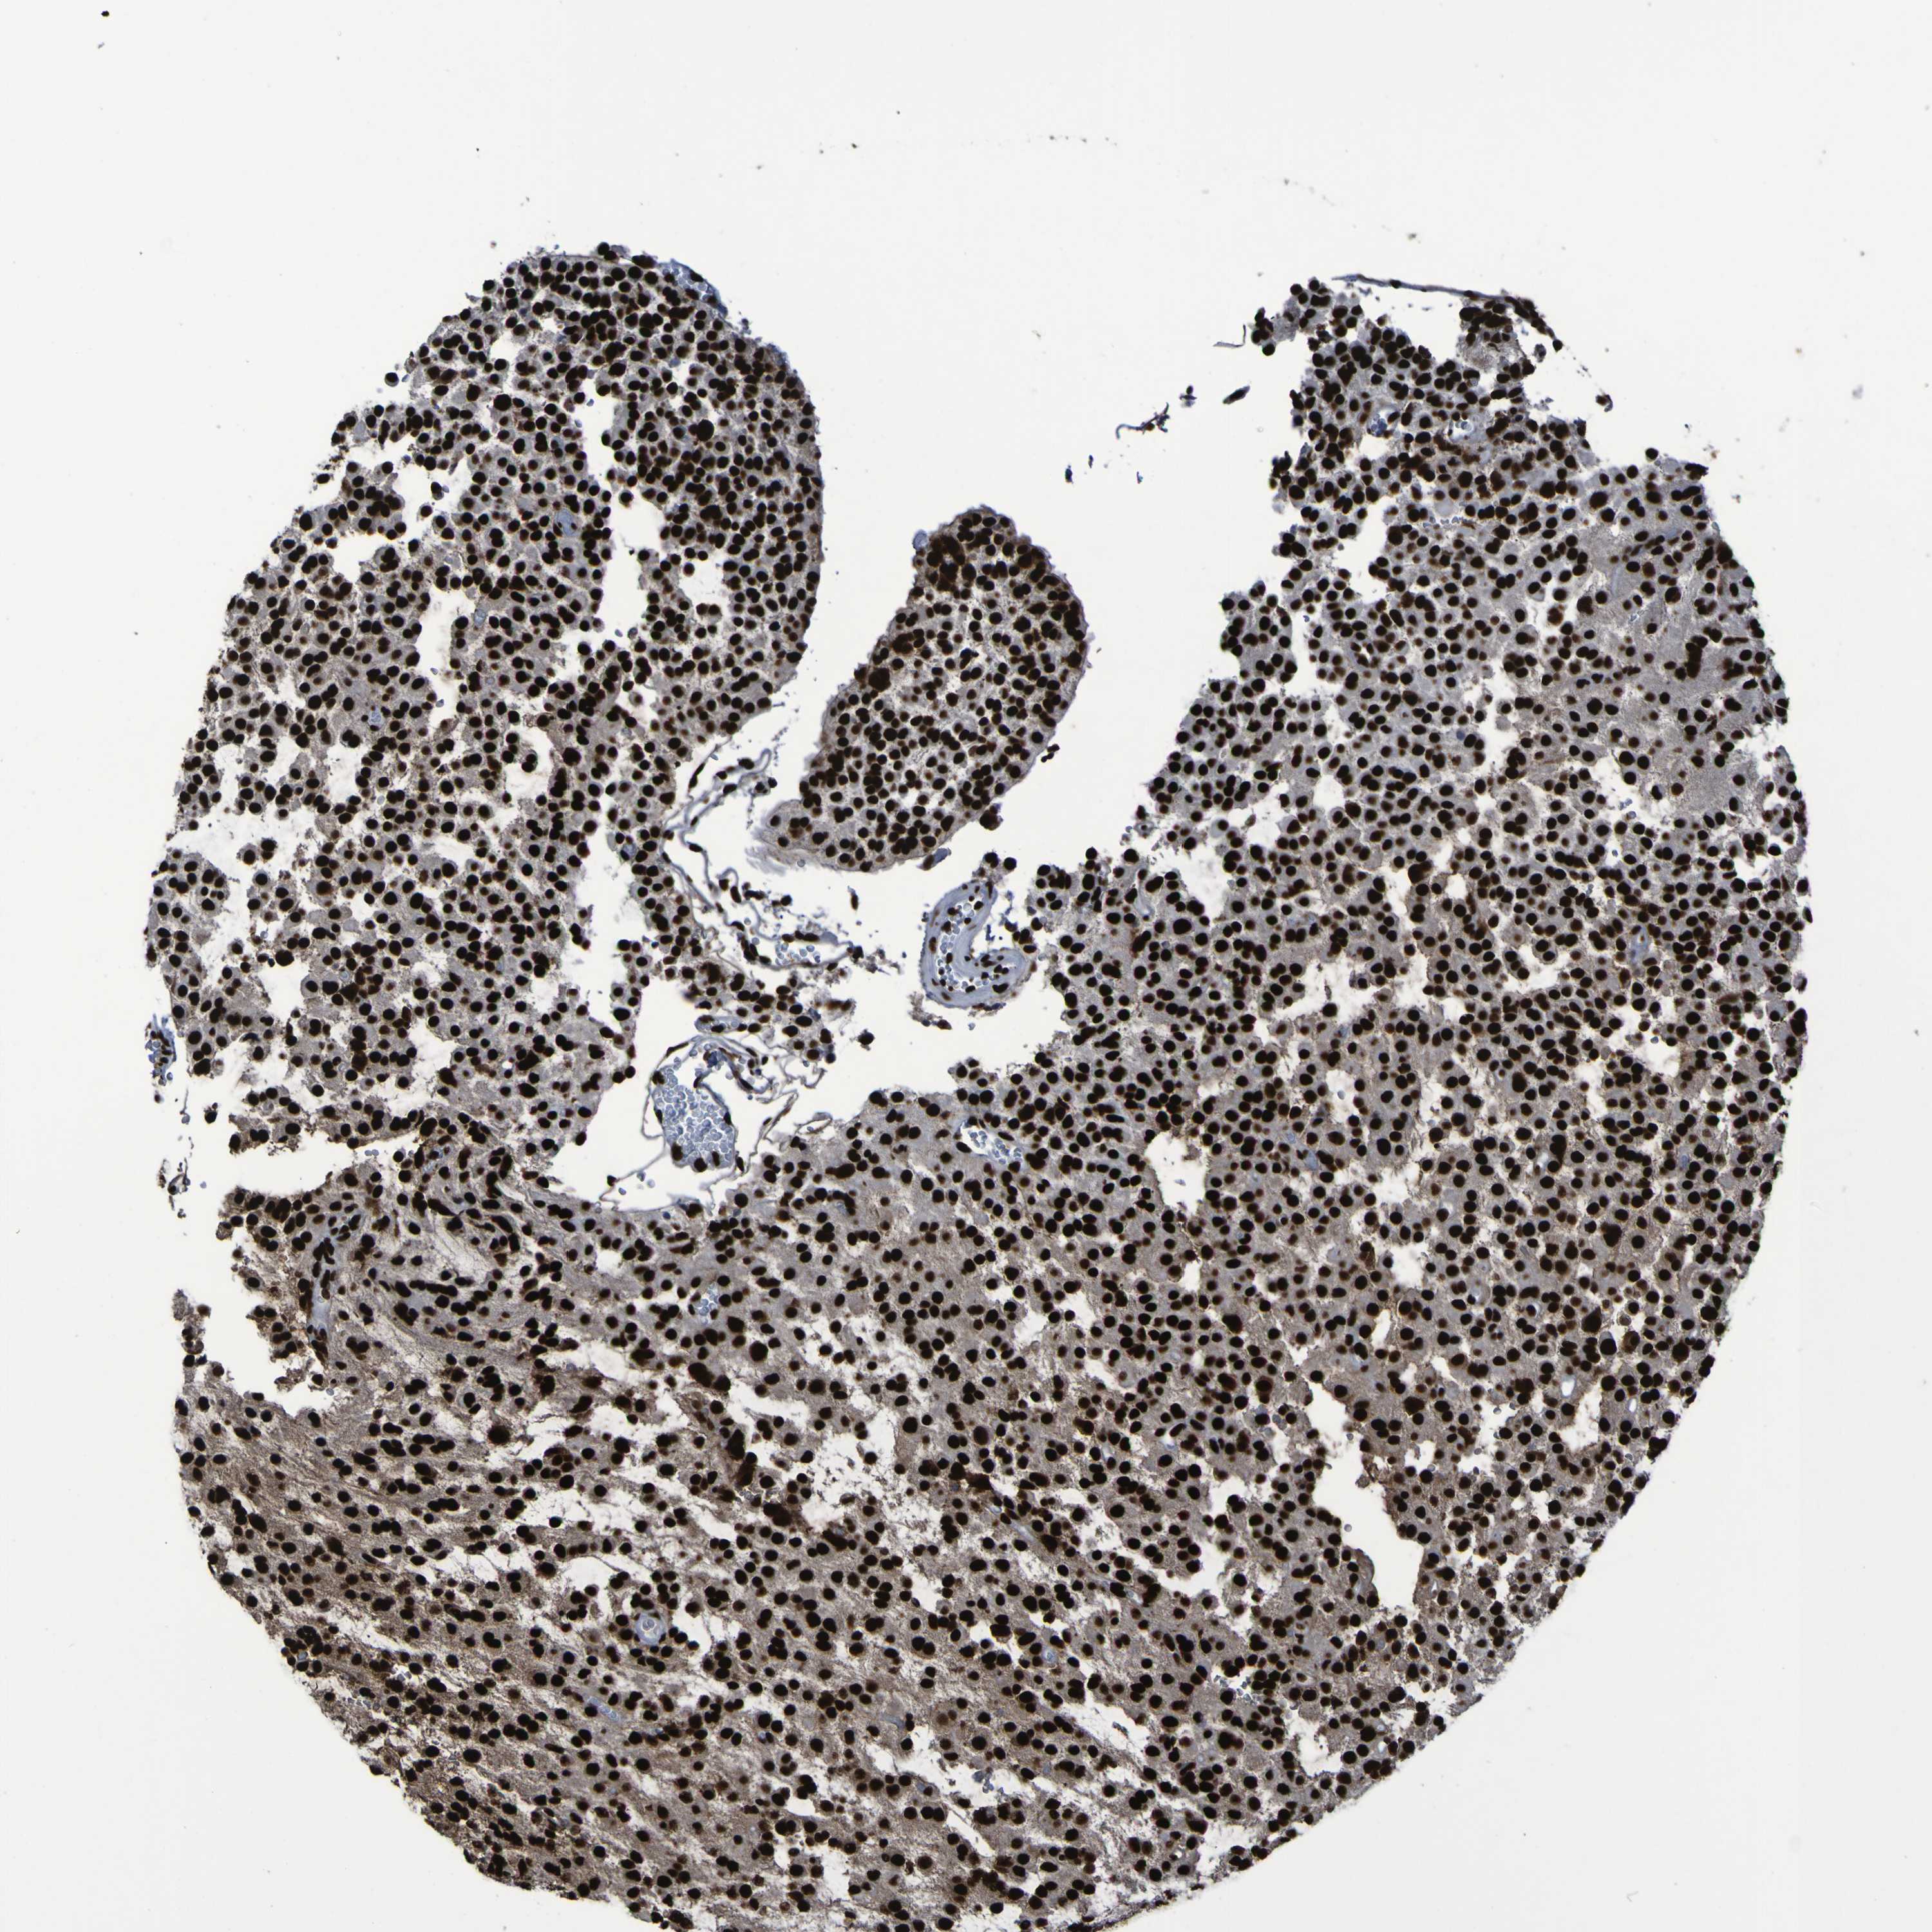

GLIOMA - Protein expressioni

A mouse-over function shows sample information and annotation data. Click on an image to view it in a full screen mode. Samples can be filtered based on level of antibody staining by selecting one or several of the following categories: high, medium, low and not detected. The assay and annotation is described here.

Note that samples used for immunohistochemistry by the Human Protein Atlas do not correspond to samples in the TCGA dataset.

Antibody stainingi

Antibody staining in the annotated cell types in the current human tissue is reported as not detected, low, medium, or high, based on conventional immunohistochemistry profiling in selected tissues. This score is based on the combination of the staining intensity and fraction of stained cells.

Each image is clickable and will lead to virtual microscopy that enables deeper exploration of all samples and also displays staining intensity scores, fraction scores and subcellular localization as well as patient and tissue information for each sample.

Antibody HPA011384

Antibody CAB012983

Staining

High

Medium

Low

Not detected

Intensity

Strong

Moderate

Weak

Negative

Quantity

>75%

75%-25%

<25%

None

Location

Nuclear

Cytoplasmic/membranous

Cytoplasmic/membranous,nuclear

Glioma, malignant, High grade

Glioma, malignant, Low grade